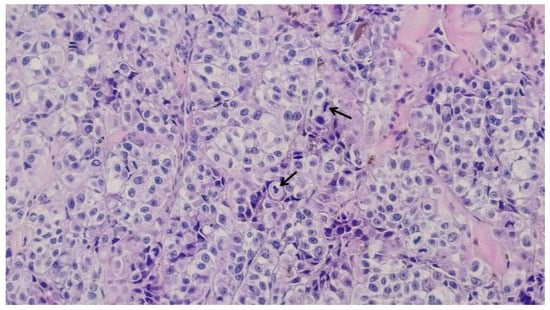

Based on the initial skin examination, a presumptive diagnosis of infected Kaposi's sarcoma was made. However, the unusual, extensive presentation prompted additional investigations. An excisional biopsy of an isolated lesion was performed to confirm the diagnosis (Figure 3 and Figure 4). The biopsy ruled out Kaposi's sarcoma and revealed the following: moderate orthokeratosis at the epidermal level, with focal pigmentation of the basal layer, and a densely cellular intradermal tumoral proliferation composed of medium to large-sized cells with abundant, frequently retracted cytoplasm. Some cells appeared ballooned, with large, prominent eosinophilic nucleoli, arranged in nests and interconnected clusters with an alveolar pattern, separated by connective-vascular septa. There was occasional discrete deposition of brown pigment, with invasion into the hypodermis, in contact with the deep excision margin. The mitotic index was less than 1/mm². Lymphatic invasion was present. There was a focal, minimal, discontinuous peritumoral lymphomononuclear inflammatory infiltrate, with limited areas of segmental tumor regression, moderate fibrosis, rare lymphocytes, and telangiectasias. These histopathological features were consistent with nodular malignant melanoma, Clark level V, with extensive involvement of the hypodermis and lymphatic spread. The biopsy specimen was sent for immunohistochemical analysis, which confirmed the diagnosis of malignant melanoma.

Figure 4. Large-sized cells with irregular hypertrophic nuclei, prominent nucleoli, and focal mitotic activity, with pigment deposition; black arrows indicate active mitoses (haematoxilin and eosin staining, 20x).